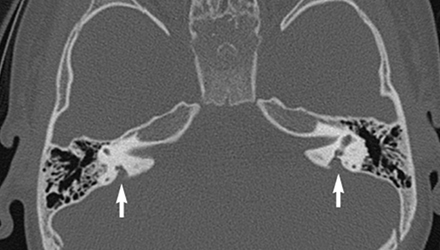

SLC26A4基因定位于人類染色體7q31,SLC26A4基因和大前庭導(dǎo)水管綜合征相關(guān)突變位點(diǎn)的發(fā)現(xiàn),證實(shí)SLC26A4是大前庭導(dǎo)水管綜合征的責(zé)任基因。

我們平時(shí)提到的“一巴掌打聾”、“一跤摔聾”其實(shí)都與SLC26A4基因突變有關(guān),絕大多數(shù)大前庭導(dǎo)水管綜合征都是SLC26A4基因突變?nèi)堑牡湣?/p>

SLC26A4基因編碼一種叫“Pendrin”的跨膜轉(zhuǎn)運(yùn)蛋白,在機(jī)體離子成分平衡的維持中發(fā)揮重要作用。

在內(nèi)耳,Pendrin表達(dá)于內(nèi)淋巴管、內(nèi)淋巴囊、橢圓囊、球囊等處,異變的蛋白將對(duì)這些結(jié)構(gòu)的正常生理功能產(chǎn)生影響,引發(fā)聽損。

SLC26A4基因突變導(dǎo)致的大前庭導(dǎo)水管綜合征的典型表現(xiàn)為兒童時(shí)期的聽力損失,90%的患者為雙側(cè)性,聽力損失程度不一,可表現(xiàn)為接近正?;蛑?極重度。

病程可為穩(wěn)定性、進(jìn)行性或波動(dòng)性,聽力可逐步下降至全聾;跌倒、撞擊等行為或無外界影響都可能引發(fā)聽力的下降。